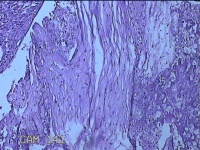

胎盘组织

孕2产39周LOP剖宫产单活胎男婴 剖宫产术

停经39周,下腹胀痛1小时。

灰白暗红色胎盘组织18x16x2.8㎝一个,表面光滑,血管清晰,颜色发暗,绒毛面结节状,轻度糜烂,表面有少许凝血块,切面见绒毛内有部分淤血,边缘蜕膜可见多个小血肿,脐带21.5x2x0.8㎝,切断脐带,见脐血管内有凝血块。